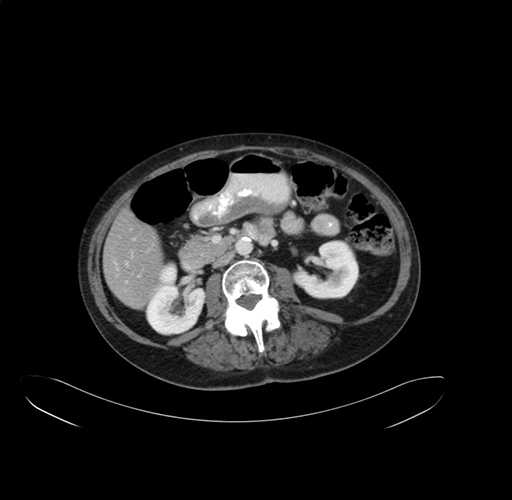

Pre-Chemo: Axial Venous

Axial Venous

Imaging analysis

Based on your CT findings, which issue(s) would give reason for "planned slowing down moment(s)" in this case?

Considering a standard right hepatectomy procedure, what step(s) of the operation would you do differently in this case?